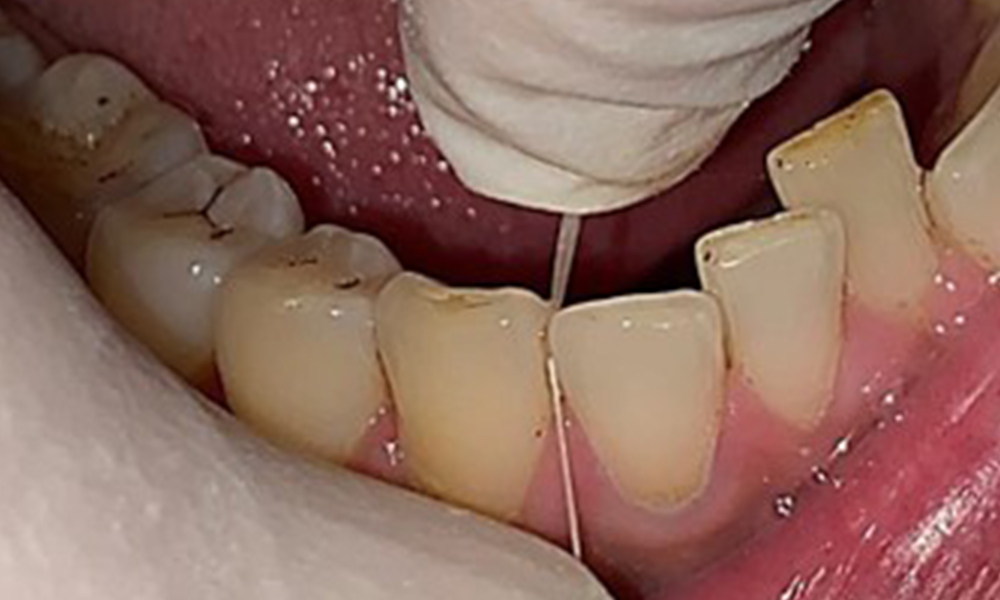

L'instruction et la motivation sont des éléments importants de ces rendez-vous. Il est important que les patients comprennent et adoptent un bon comportement en matière d'hygiène intrabuccale à domicile. L'accumulation de plaque est particulièrement évidente dans les régions cervicales (Fig. 8).

Il convient d'en discuter avec le patient et d'améliorer la technique de brossage des dents. Il est recommandé d'utiliser une brosse à dents souple pour l'hygiène intrabuccale à domicile en raison de la présence d'érosions et d'attritions.